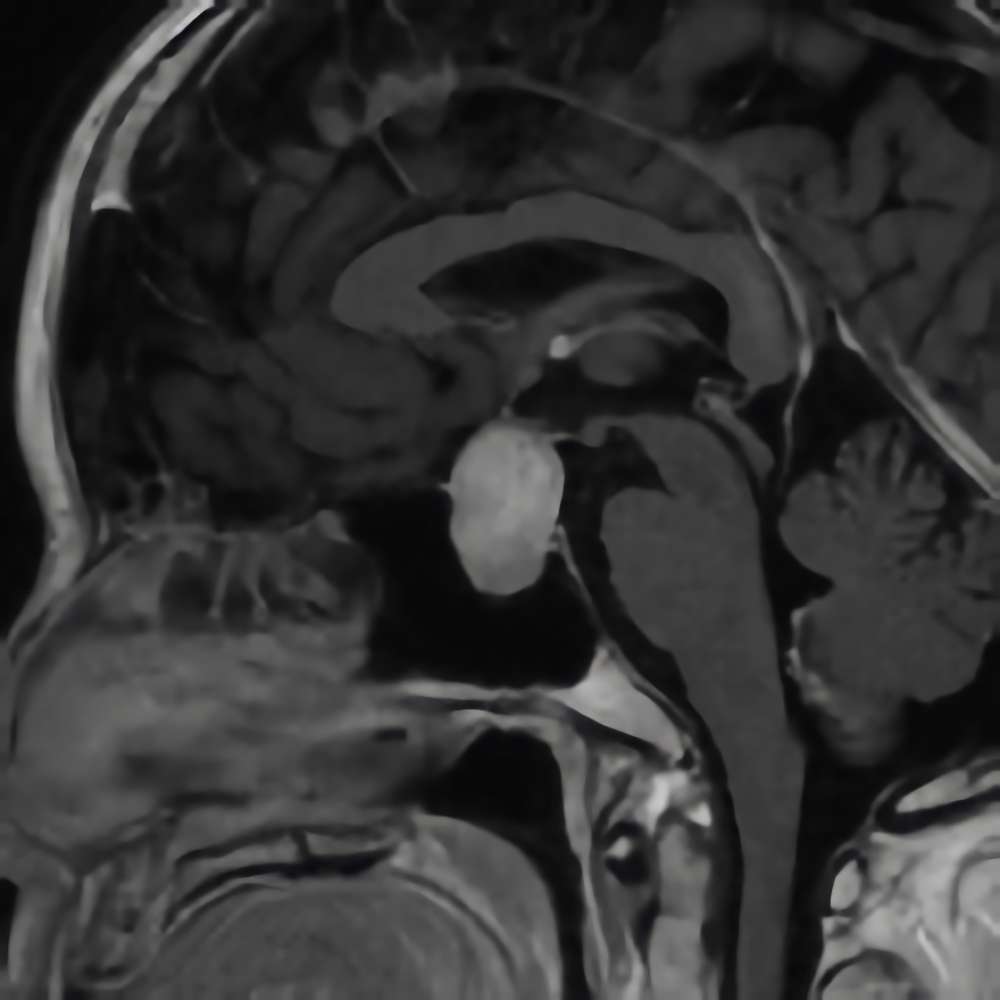

下垂体腺腫

No.’16_38 手術前1

No.’16_38 摘出 前

No.’16_38 摘出 後